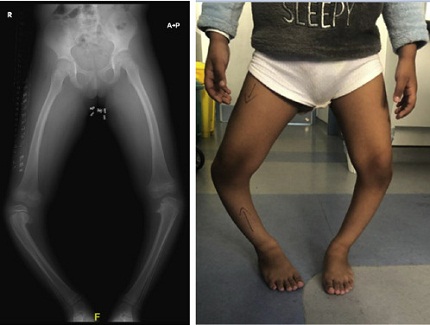

Penyakit Blount adalah gangguan pertumbuhan pada lempeng pertumbuhan bagian dalam tulang kering (tibia). Gangguan ini menyebabkan pertumbuhan tulang tidak seimbang sehingga tungkai bengkung pada anak semakin jelas seiring waktu. Deformitas biasanya berbentuk huruf O dan terpusat pada area lutut.

Penyakit Blount dapat muncul sejak usia dini (tipe infantile, usia 1–4 tahun) atau pada usia lebih besar dan remaja (tipe juvenile dan adolescent). Pada tipe infantile, tungkai bengkung pada anak sering terjadi pada kedua sisi, sedangkan pada tipe remaja dapat terjadi hanya pada satu tungkai.

Tanda utama penyakit Blount adalah tungkai bengkung pada anak yang semakin nyata dan tidak berkurang seiring bertambahnya usia. Kelengkungan biasanya tampak jelas saat anak berdiri atau berjalan.

Selain deformitas, dapat ditemukan perbedaan derajat bengkok antara tungkai kanan dan kiri. Anak mungkin tampak berjalan dengan posisi lutut terbuka atau mengalami perubahan pola berjalan. Pada tahap awal, nyeri jarang dikeluhkan, sehingga orang tua sering tidak menyadari adanya gangguan pertumbuhan tulang.